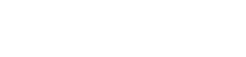

我熟练地启动了实验室颜值最高的小动物能谱CT设备,开始扫描。期间我脑补了X射线光子一个个穿过螃蟹被探测器逐个转化成电荷、放大、成形、能量甄别、计数、数据采集的画面。

蟹壳、蟹黄和蟹肉的有效原子序数和密度不同,在CT图像中的灰度不同,可以区分。而我们研发的光子计数型能谱CT更胜一筹,通过多能区扫描,还可以进行有效原子序数测量,进行物质分解,把蟹黄和蟹肉分得更清楚。

设备采用了先进的光子计数能谱成像技术,结合能量权重成像以及K边成像等算法,能够有效区分不同软组织等衰减系数相近的物质,减少了伪影的产生。与传统积分型探测器相比,提高了CT重建图像的信噪比和对比度的同时,还可以进行物质分解和吸收边成像。